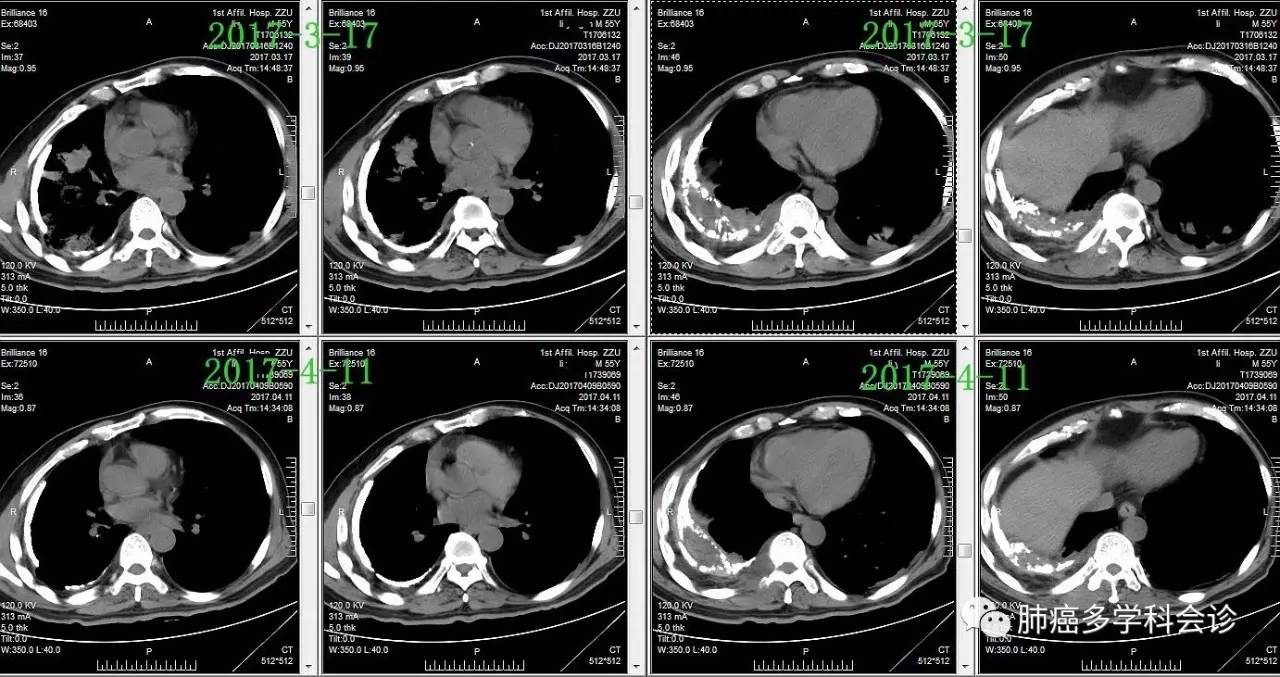

以下化疗前1周(2017-3-17)和第一周期化疗结束后(2017-4-11)两肺转移灶和右胸膜腔病灶的变化: